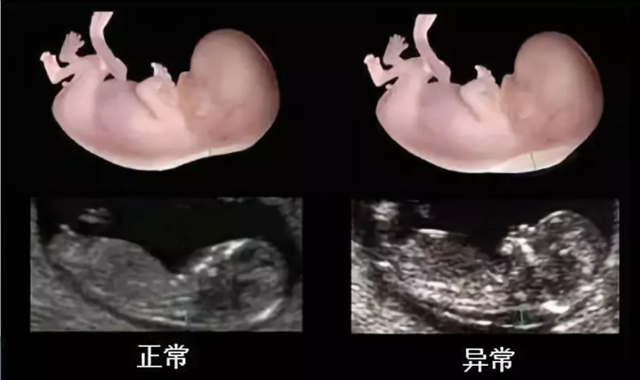

胎儿颈后透明层的厚度,与染色体和其他病变密切相关。临床研究发现,在唐氏患儿中,约75%的胎儿颈项透明层出现明显增厚。

临床上,胎儿NT值≥3mm,即可判断为异常。

一般建议,当胎儿NT值≥2.5mm时,即可咨询医生专业意见,决定是否进行进一步检查。

研究发现,大约有75%患唐氏综合征的宝宝通过这一方法被正确识别出来。

②先天性心脏病

先天性心脏病胎儿的颈项透明层会增厚。10~14周是胎儿心脏发育成熟的一个重要阶段。

如果胎儿心脏存在缺陷,加上此阶段胎盘外周阻力较高,心负荷加重,静脉压升高和淋巴回流不畅,会导致早期心衰和颈项透明层增厚。